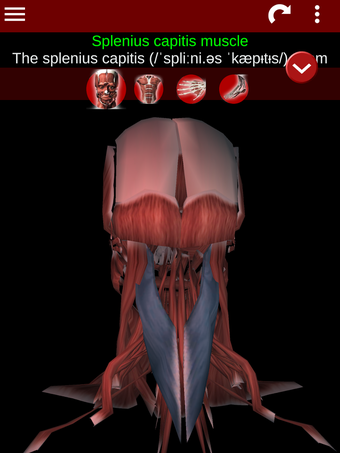

Esta herramienta educativa proporciona una descripción de cada músculo del cuerpo humano, así como un modelo tridimensional del sistema muscular. Con sólo tocar con el dedo, la aplicación revelará la información pertinente.

Los usuarios pueden hacer zoom sobre el músculo, así como elegir si ocultar o mostrar los datos. La orientación puede ser horizontal o vertical, según convenga más.